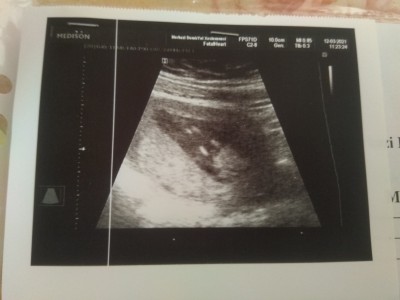

Merhaba arkadaslar. 12 haftalik ultrason goruntusu bebegin. Doktor popo altindan cekmeye calisti bebek biraz haraketliydi yakalaya bildigi kadarini cekti. Sizinde fikirlerinizi merak ediyorum.

Doktorunuz demedi mi erkeğe benzettim ama bilemem tabi

Devlet hastanesine gittim doktor erkege benzetiyorum dedi ama net soyleyemem daha erken dedi. Ama ben erkege benzettim dedi.

Eğitimini alan doktor bile emin olamamış, ben şahsen bir şey diyemem, tek bir görüntüden..

18 haftalık Ken cinsiyeti tam net belli olur biz bişey diyemeyiz doktor bilir